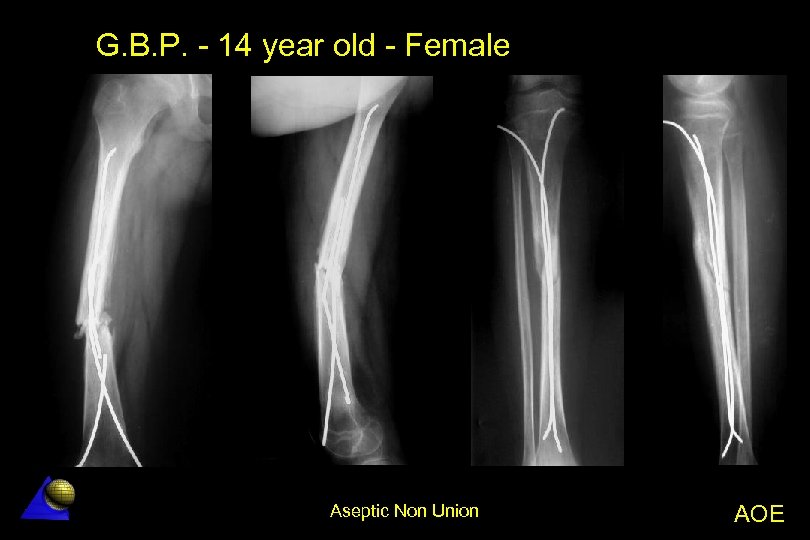

G. B. P. - 14 year old - Female Femur diaphysis non-union - 11. 01 l Motorcycle accident â l Treated in another Hospital â l (Right femur and tibia fractures) Kirschner wire nailing of femur and tibia At 6 months post-op Femur angulation with a broken K wire â Femoral non-union â Tibia fracture was healed â Aseptic Non Union AOE

G. B. P. - 14 year old - Female Femur diaphysis non-union - 11. 01 l Surgical treatment â Femur and tibia nails removal â Decortication + LC-DCP axial compression plating â Cancellous bone screws were used (osteoporosis) â Autologouu bone grafting l Excellent result at 12 and 24 months Aseptic Non Union AOE

G. B. P. - 14 year old - Female Aseptic Non Union AOE

G. B. P. - 14 year old - Female 0 m 0 m Tibia healed. Decortication, axial compression plate fixation. Aseptic Non Union AOE

G. B. P. - 14 year old - Female 3 m 6 m Aseptic Non Union AOE

G. B. P. - 14 year old - Female 12 m Aseptic Non Union AOE

G. B. P. - 14 year old - Female 24 m Aseptic Non Union AOE